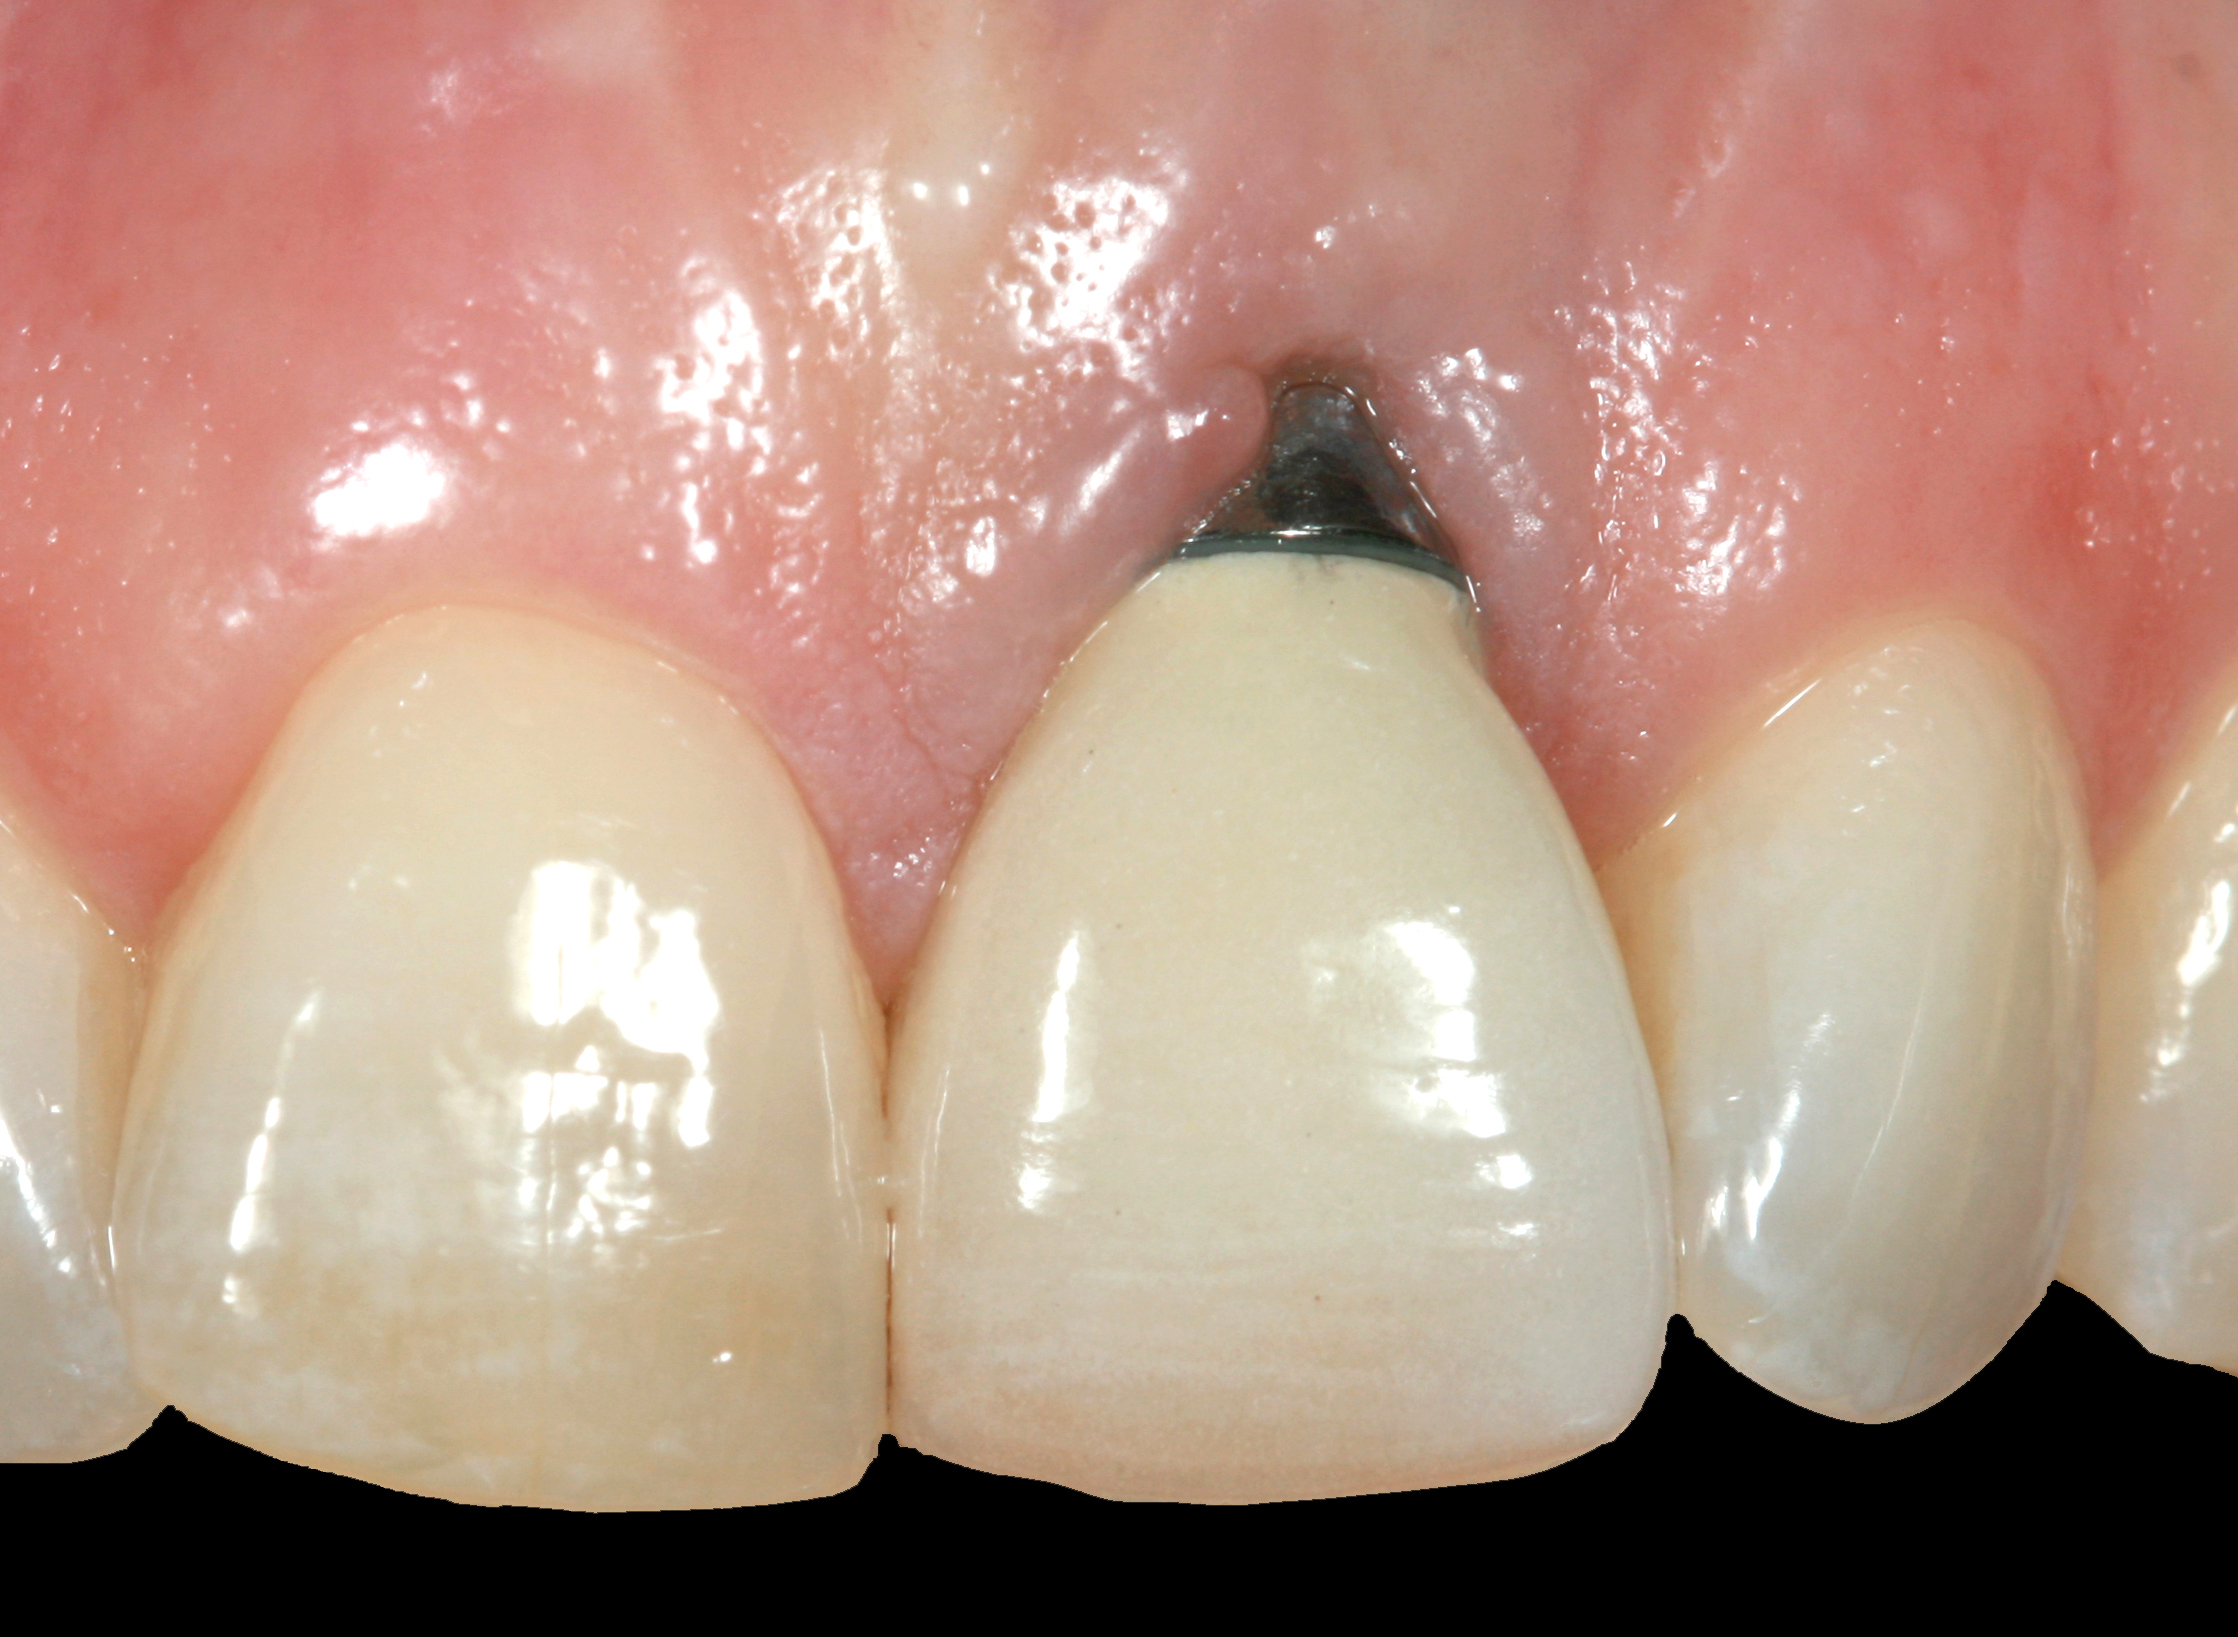

The following case report provides an example of this case scenario: A 24-year-old white male presented with congenitally missing tooth No. 26 restored with a single-tooth cement-retained implant restoration. The implant was placed excessively to the facial aspect of the edentulous site and too shallow, and the periodontal phenotype was thin scalloped (Figure 32). In an effort to mimic the lost midfacial soft tissues, pink ceramics were used as a cosmetic facade. Even though the restoration was not in the esthetic zone, the patient was highly displeased with the esthetic outcome and sought remediation.

The crown and screw-retained custom abutment were removed, and a surgical cover screw was placed into the implant, thereby allowing spontaneous gingival augmentation in situ (Figure 33 and Figure 34). Note that the lingual aspect of the implant site was significantly more coronal than the labial aspect, which was positive because the defect would be limited to a facial–lingual defect. A fixed RBR bridge was cemented on the adjacent teeth and used as a tooth-supported transitional provisional restoration (Figure 35). A few weeks were allotted to let the soft tissue heal and migrate around the cover screw (Figure 36) to see if there would be complete coverage, thereby allowing a soft-tissue augmentation procedure to be performed with primary flap closure as in clinical scenario No. 2. The major obstacle in achieving a positive tissue response was that the implant depth was also deficient because the implant–abutment connection was at the level of the free gingival margin. It was decided that the best treatment option would be to remove the implant. A high-powered reverse-torque device (Fixture Remover Kit, NeoBiotech, www.neobiotechus.com) was used to remove the implant atraumatically (Figure 38 through Figure 41). The implant socket was allowed to heal for several months not unlike an extracted tooth (Figure 42). A new implant was placed in a better position from both a restorative and esthetic perspective (Figure 43), and after a few months of healing, a new crown was made (Figure 44). A satisfactory functional and esthetic result was achieved (Figure 45 and Figure 46) without employing pink porcelain.

Fig 32. A dissatisfied patient presented with significant midfacial recession of implant restoration of tooth No. 26. Pink ceramic material was used unsuccessfully to prosthodontically compensate for the lost midfacial tissue.

Figure 32